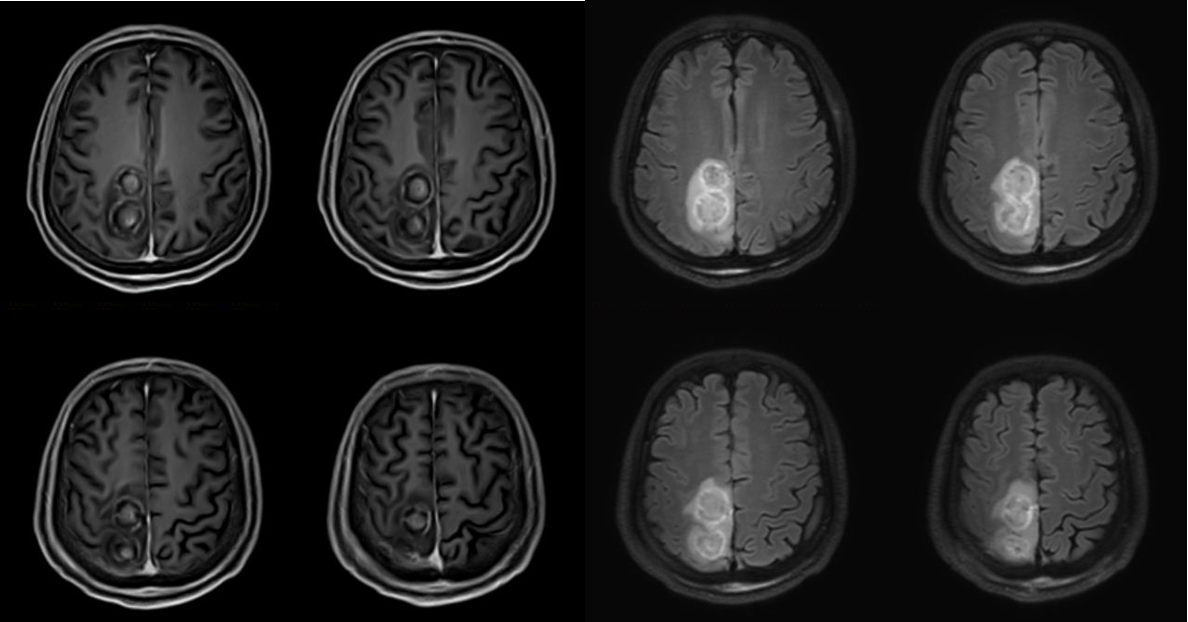

手术当天,在医院的复合手术间,医疗团队通过神经导航精准定位后,通过颅骨上毫米级的小孔,按照计划路径将光纤准确置入肿瘤内部,在磁共振实时成像的监测下,按照计划对肿瘤进行消融,手术全过程不到2小时。

“在手术中,磁共振成像实时监测可以让我们实时观看消融效果,进行及时的反馈和调整,既满足安全性,又可以达到最佳的效果,手术时间比传统的开颅手术缩短了至少一半。”周大彪说。手术后,王先生很快清醒,自述原本活动受限的左下肢比手术前轻松许多;大约8小时后CT检查未见颅内出血等情况;术后第三天,北京天坛医院神经外科学中心主任江涛和医疗团队一起专门查看王先生情况,发现他左下肢远端肌力恢复良好,预示神经功能恢复的可能性很大,江涛建议密切随访观察远期效果,患者头部微小伤口无缝合线、愈合良好,无颅内感染表现;手术一周后,王先生复查磁共振后顺利出院。